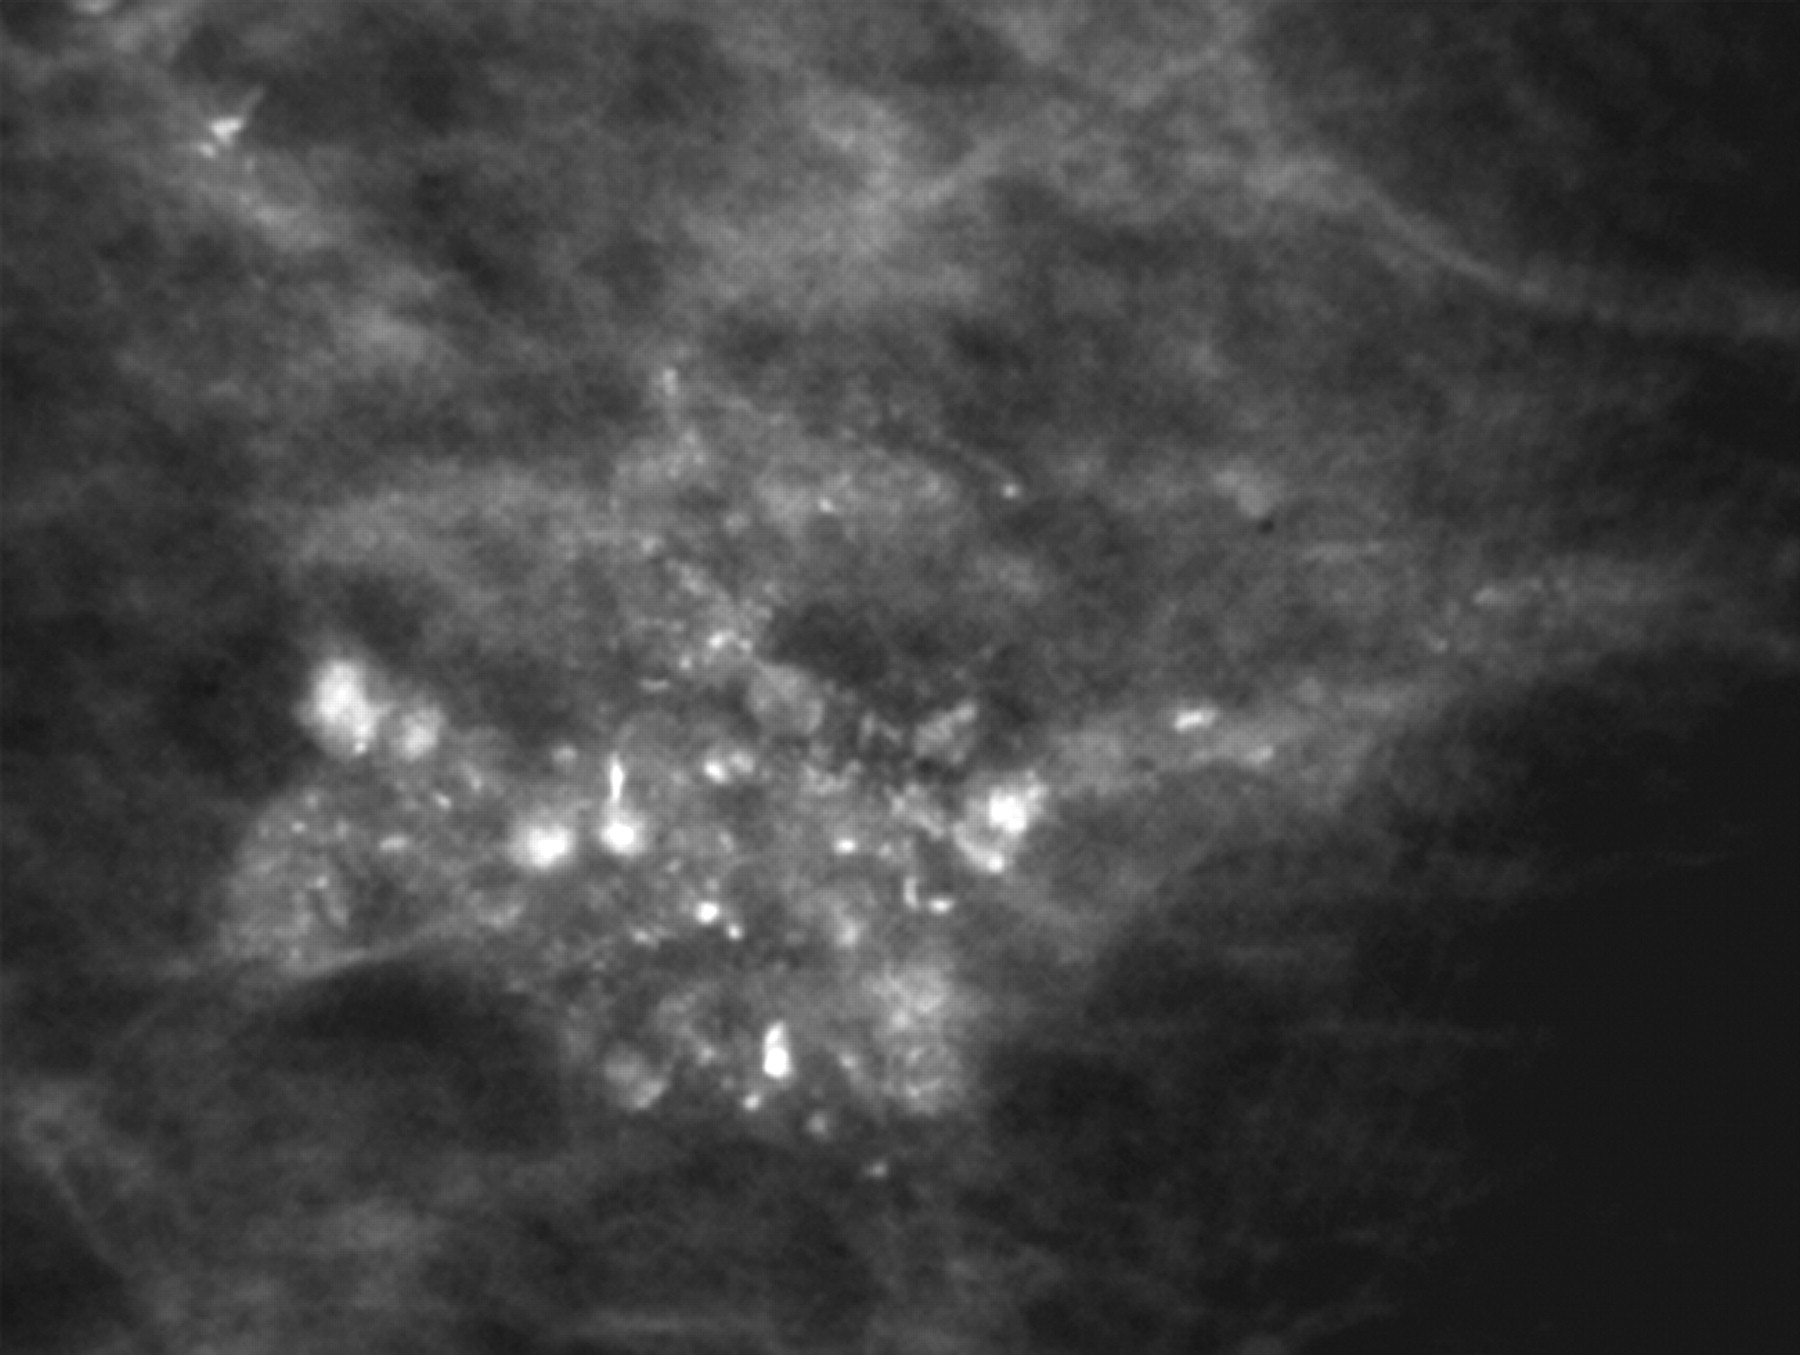

미세석회변화(Microcalcification)

위 사진은 유방촬영 영상에서 미세석회 변화 부분을 확대한 것으로 하얗게 보이는 부분들이 불규칙하게 분포되어 있는 것을 확인할 수 있다. 이와 같이 유방촬영술은 유방초음파 상에서는 발견할 수 없는 유방암에 동반되는 미세석회 변화를 발견할 수 있다는 장점을 가지고 있습니다.